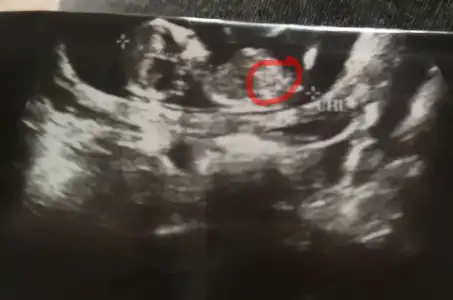

Buda şimdiki hamileliğim işaretlediğim yer nubsa erkeğe uyuyor, daha cinsiyet öğrenmedik

• _20190312_000258.webp